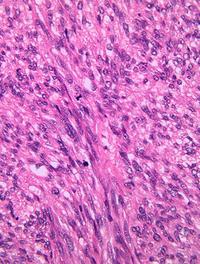

Les « gastrointestinal stromal tumors » (GIST) sont les plus fréquentes des tumeurs mésenchymateuses du tractus digestif, mais ne représentent [...]